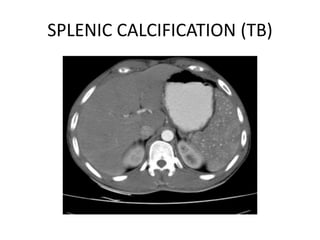

Splenic Calcification

• Calcification in or adjacent to the spleen is common,

especially after age of 50. Calcific plaque in splenic

artery are frequent chance findings on abdominal X-

rays.

• Splenic vein calcification is uncommon but may follow

portal pyaemia or splencetomy.

• Splenic TB granulomas may produce single or multiple

well defined calcification in the parenchyma on X-ray.

• Splenic cyst may show curvilinear or oval calcification.

• A complete infarcted spleen appears as small curved

calcified structure.

SPLENIC CALCIFICATION (TB)